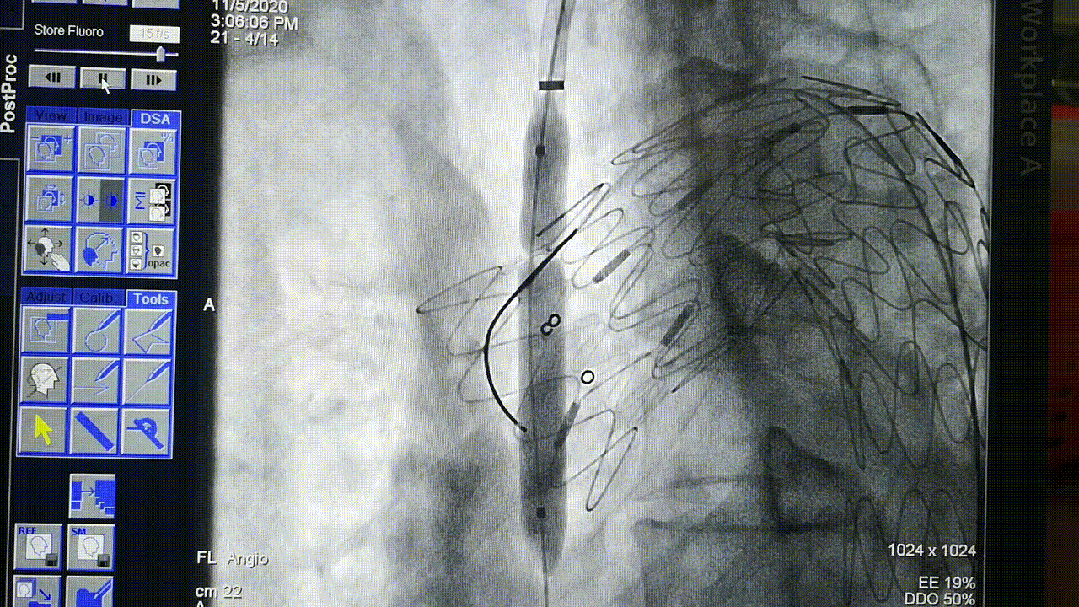

导丝破膜,各角度反复确认

机械破膜和激光破膜

破膜装置开窗

转播手术过程中即便熟练团队开窗,时间不可控,导丝穿破FUSTAR